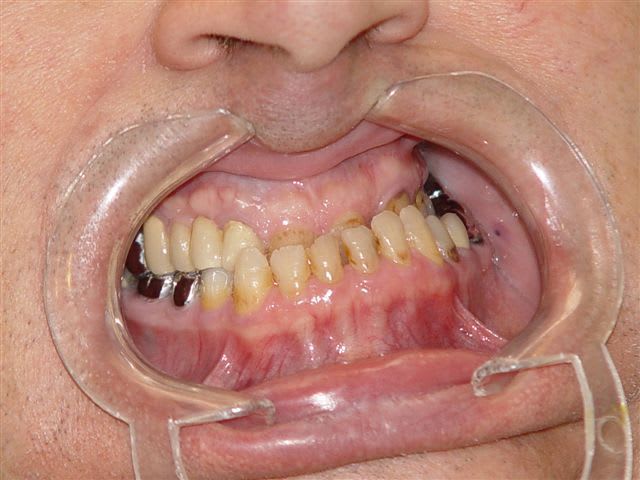

que feriez vous dans ce cas, les photos parlent d'elles mêmes

J'ai reçu ce patient en mai 2006

Tout d'abord évaluation de la hauteur d'occlusion fonctionnelle à l'aide de cire à boxer on laisse le patient avaler sa salive pendant 10 mn, puis arc facial et montage sur articulateur Artex, wax up et reconstitution prothétique temporaire des dents postérieures.

Validation de cette nouvelle occlusion par le patient pendant 6 mois puis si tout baigne prothèse fixe céramique, globale dans ce cas.

Cas terminé en décembre 2006, revu la semaine dernière, ce qui m'a donné envie de vous le montrer.